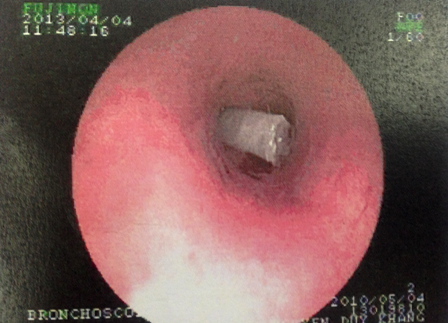

Chiếc béc thổi nằm chắn ngang trong phế quản bệnh nhi

Tại đây, sau khi khai thác bệnh sử và dựa theo xác nhận của người mẹ về việc cây kèn bé chơi trước đó đã bị mất một mẫu ở đầu kèn, nghi ngờ trẻ bị hóc dị vật, bác sĩ tiến hành chụp X-quang kiểm tra. Tuy nhiên hình ảnh X-quang hoàn toàn bình thường. Những lần thăm khám tiếp theo, qua ống nghe tim phổi, bác sĩ ghi nhận có âm thanh lạ “te… te” (tiếng của không khí khi thổi qua một ống hẹp và rỗng) phát ra từ trong phổi của bé.

Sau khi hội chẩn nhanh, bác sĩ quyết định điều trị bằng kháng sinh và kháng viêm tích cực để đẩy lùi tình trạng ho khò khè. Ngay sau đó, bệnh nhi được chỉ định nội soi kiểm tra phế quản. Đường đi của ống nội soi đã bị cản ngang bởi một mẫu nhựa trắng hình ống dính đầy đàm nhớt. Dị vật nhanh chóng được gắp ra ngoài và xác định đó là chiếc béc thổi gắn phía trong đầu kèn để tạo âm thanh khi thổi. Sau khi gắp được dị vật ra ngoài tình trạng của bé K. đã ổn định.